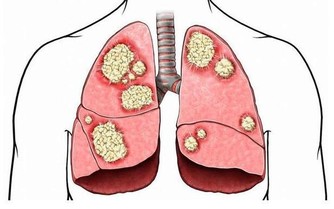

身體中的毒素,也可說是(污染物),多半是人體在吸收食品後,

進行新陳代謝中的產物,這就是『吃得多,病也多;吃得好,死得早』的道理,

它們往往停留在血管、肌肉、筋骨、關節以及臟腑的空隙中。